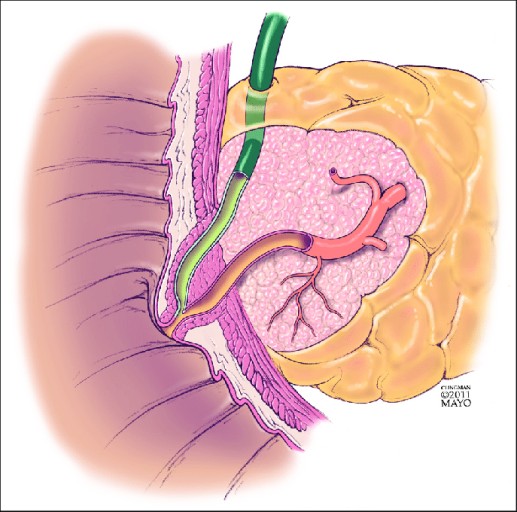

췌장암 초기증상 - 황달

- 설명: 췌장암이 췌장의 머리 부분(췌두부)에 생겨 담즙이 흐르는 총담관을 막을 때 발생합니다. 피부와 눈의 흰자위가 노랗게 변하고, 소변 색이 콜라처럼 짙어지며, 대변 색이 회색이나 하얗게 변하는 증상이 나타납니다. 황달은 비교적 초기에 발견될 수 있는 중요한 신호입니다.

- 복합적인 증상 주의: 단순 소화 불량이 아닌, 복부 통증 + 체중 감소 + 황달 + 새로운 당뇨병 등 여러 증상이 복합적으로 나타나면 즉시 병원을 찾아 정밀 검사(복부 CT, MRI, 내시경 초음파 등)를 받아야 합니다.